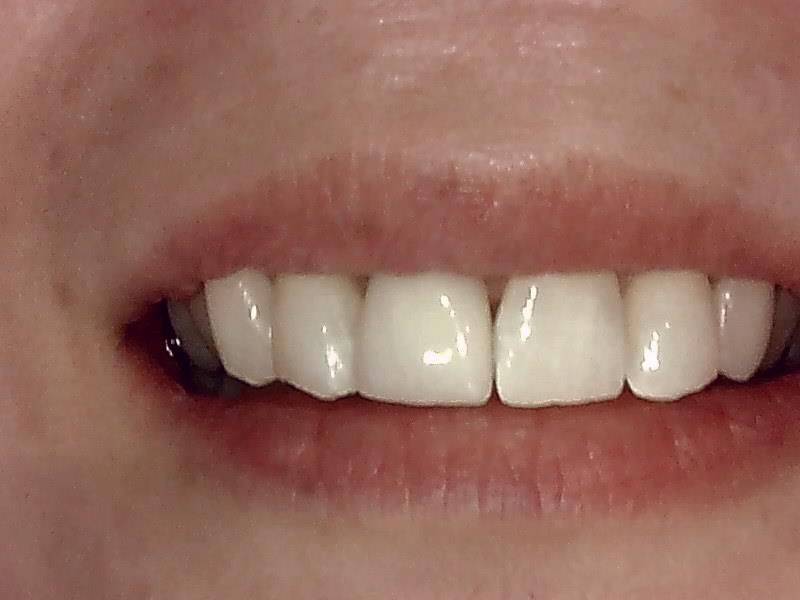

写真; ジルコニアセラミック冠装着

完成

治癒